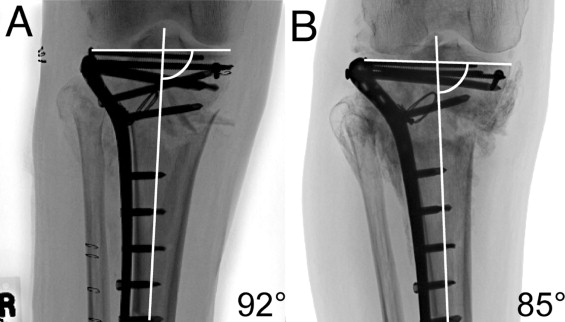

Fracture pattern and fixation type related to loss of reduction in bicondylar tibial plateau fractures